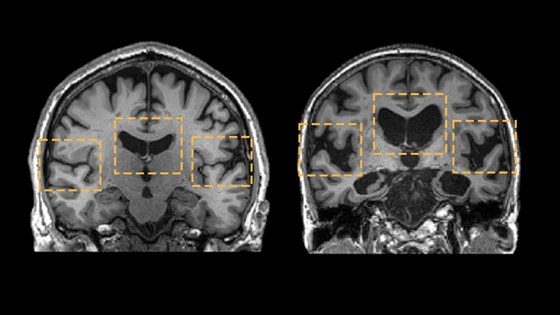

중년은 뇌 노화의‘가속 구간’이다.연구들을 종합해 보면,뇌는 나이에 따라 일정하게 늙지 않는다.어떤 시기에는 완만하게,어떤 시기에는 갑자기 확 꺾인다.그 급격한 하강 구간이 바로 40대 전후다.이때 해마와 백질 같은 핵심 부위의 부피가 빠르게 줄어들기 시작한다.해마는 기억과 감정,자아 정체성을 담당하는 곳이다.이곳이 위축되면,단순히 기억력이 나빠지는 걸 넘어‘내가 누구인지’에 대한 감각까지 흐려질 수 있다.

전두엽도 예외가 아니다.계획,판단,감정 조절을 담당하는 전두엽은 가장 늦게 발달하는 동시에,가장 먼저 퇴화하는 영역이다.그래서 중년 이후 “예전 같지 않다”는 느낌이 드는 건 착각이 아니다.실제로 뇌의 구조와 연결망이 바뀌고 있기 때문이다.

여성에게 중년은 더 극적이다.폐경을 기점으로 뇌의 에너지 대사 방식이 바뀌고,해마 부피는 줄어들며,백질에 부담이 늘어난다.이 변화는 눈에 보이지 않게 진행되지만,훗날 기억력 저하와 인지 기능 저하로 이어질 가능성을 높인다.

문제는,이 모든 변화가 아무 경고 없이 시작된다는 점이다.대부분의 사람은 60대가 돼서야 “뇌가 예전 같지 않다”고 느낀다.하지만 그때는 이미 많은 변화가 되돌릴 수 없는 단계에 접어든 뒤다.그래서 최근의 치매 연구는 노년이 아니라 중년의 뇌를 주목하기 시작했다.

이 시기에 어떤 선택을 하느냐에 따라,뇌 노화는 완만해질 수도 있고 폭주할 수도 있다.실제로 같은 나이,같은 유전자를 가진 사람들 사이에서도 중년 이후부터 격차는 급격히 벌어진다.누군가는 50대에도 또렷한 기억력과 판단력을 유지하는 반면,누군가는 눈에 띄게 늙는다.